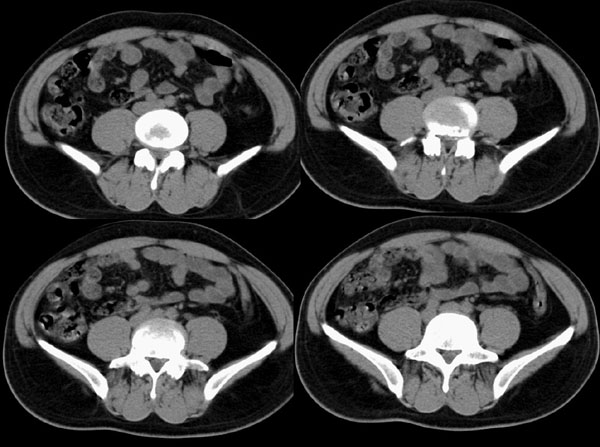

m29y平常体健,无明显不适。单位体检时发现左肾区病变。来我院作ct如下(病人不做增强):

左肾区囊肿冠、矢状重建: